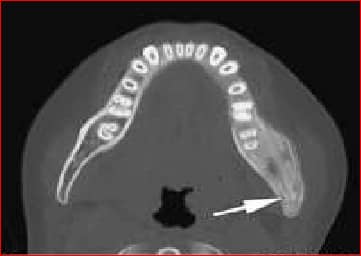

Image shows:

First:Sequestrum: Large Devascularised fragment of bone separated from the healthy bone after undergoing ischemic necrosis.

Second:Involucrum: New bone deposited around a sequestrum, resulting from cortical damage stimulating the periosteum to lay down new bone, and surround the sequestrum.

Third: Brodie’s Abscess: Focal Abscess, most commonly found in metaphyses of a long bone.

Identify this condition:

Ans:C.)Garre’s sclerosing osteomyelitis.

Garre’s sclerosing osteomyelitis

- This is a sclerosing, non-suppurative chronic osteomyelitis.

- It is a chronic osteomyelitis with subperiosteal bone and collagen deposition.

- It may begin with acute local pain,pyrexia and swelling. Pyrexia and pain subside but the fusiform osseous enlargement persists.

- There is tenderness on deep palpation. There is no discharging sinus.

- This disease entity is well-described in dental literature and is commonly associated with an odontogenic infection resulting from dental caries

- Treatment is guarded. Acute symptoms subside with rest and broad-spectrum antibiotics. Sometimes, making a gutter or holes in the bone bring relief in pain.